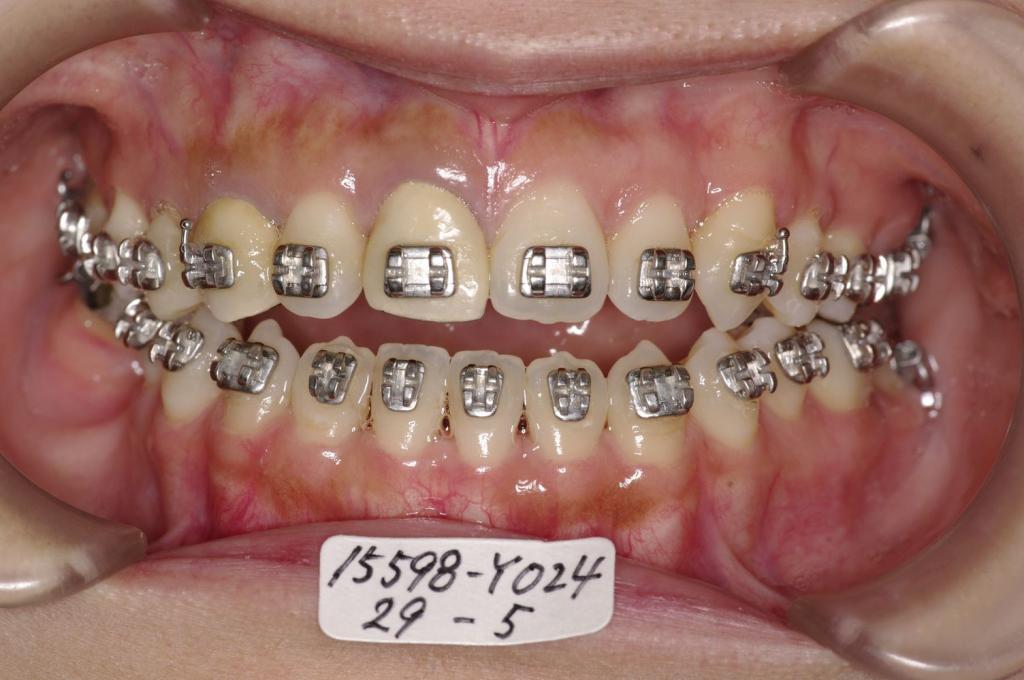

- 顎、顔の歪みの矯正治療

- 咬み合わせが悪い